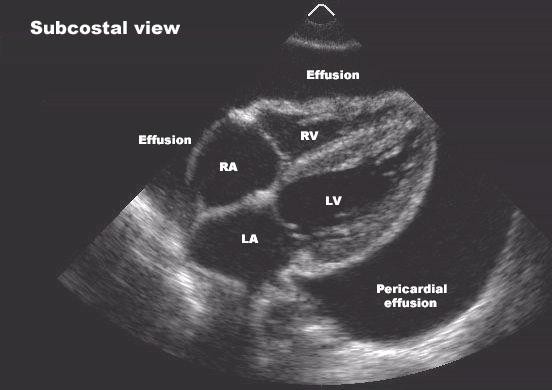

– Evaluation of pericardial conditions: i.e. pericardial effusion, constrictive pericarditis.

Other Uses: Echocardiography is useful in the diagnosis of fluid in the pericardium (the sac that surrounds the heart). It also determines when the problem is severe and potentially life-threatening. Other diagnoses (plural for diagnosis) made by Doppler or echocardiography include congenital heart diseases, blood clots or tumors within the heart, active infection of the heart valves, abnormal elevation of pressure within the lungs, etc.